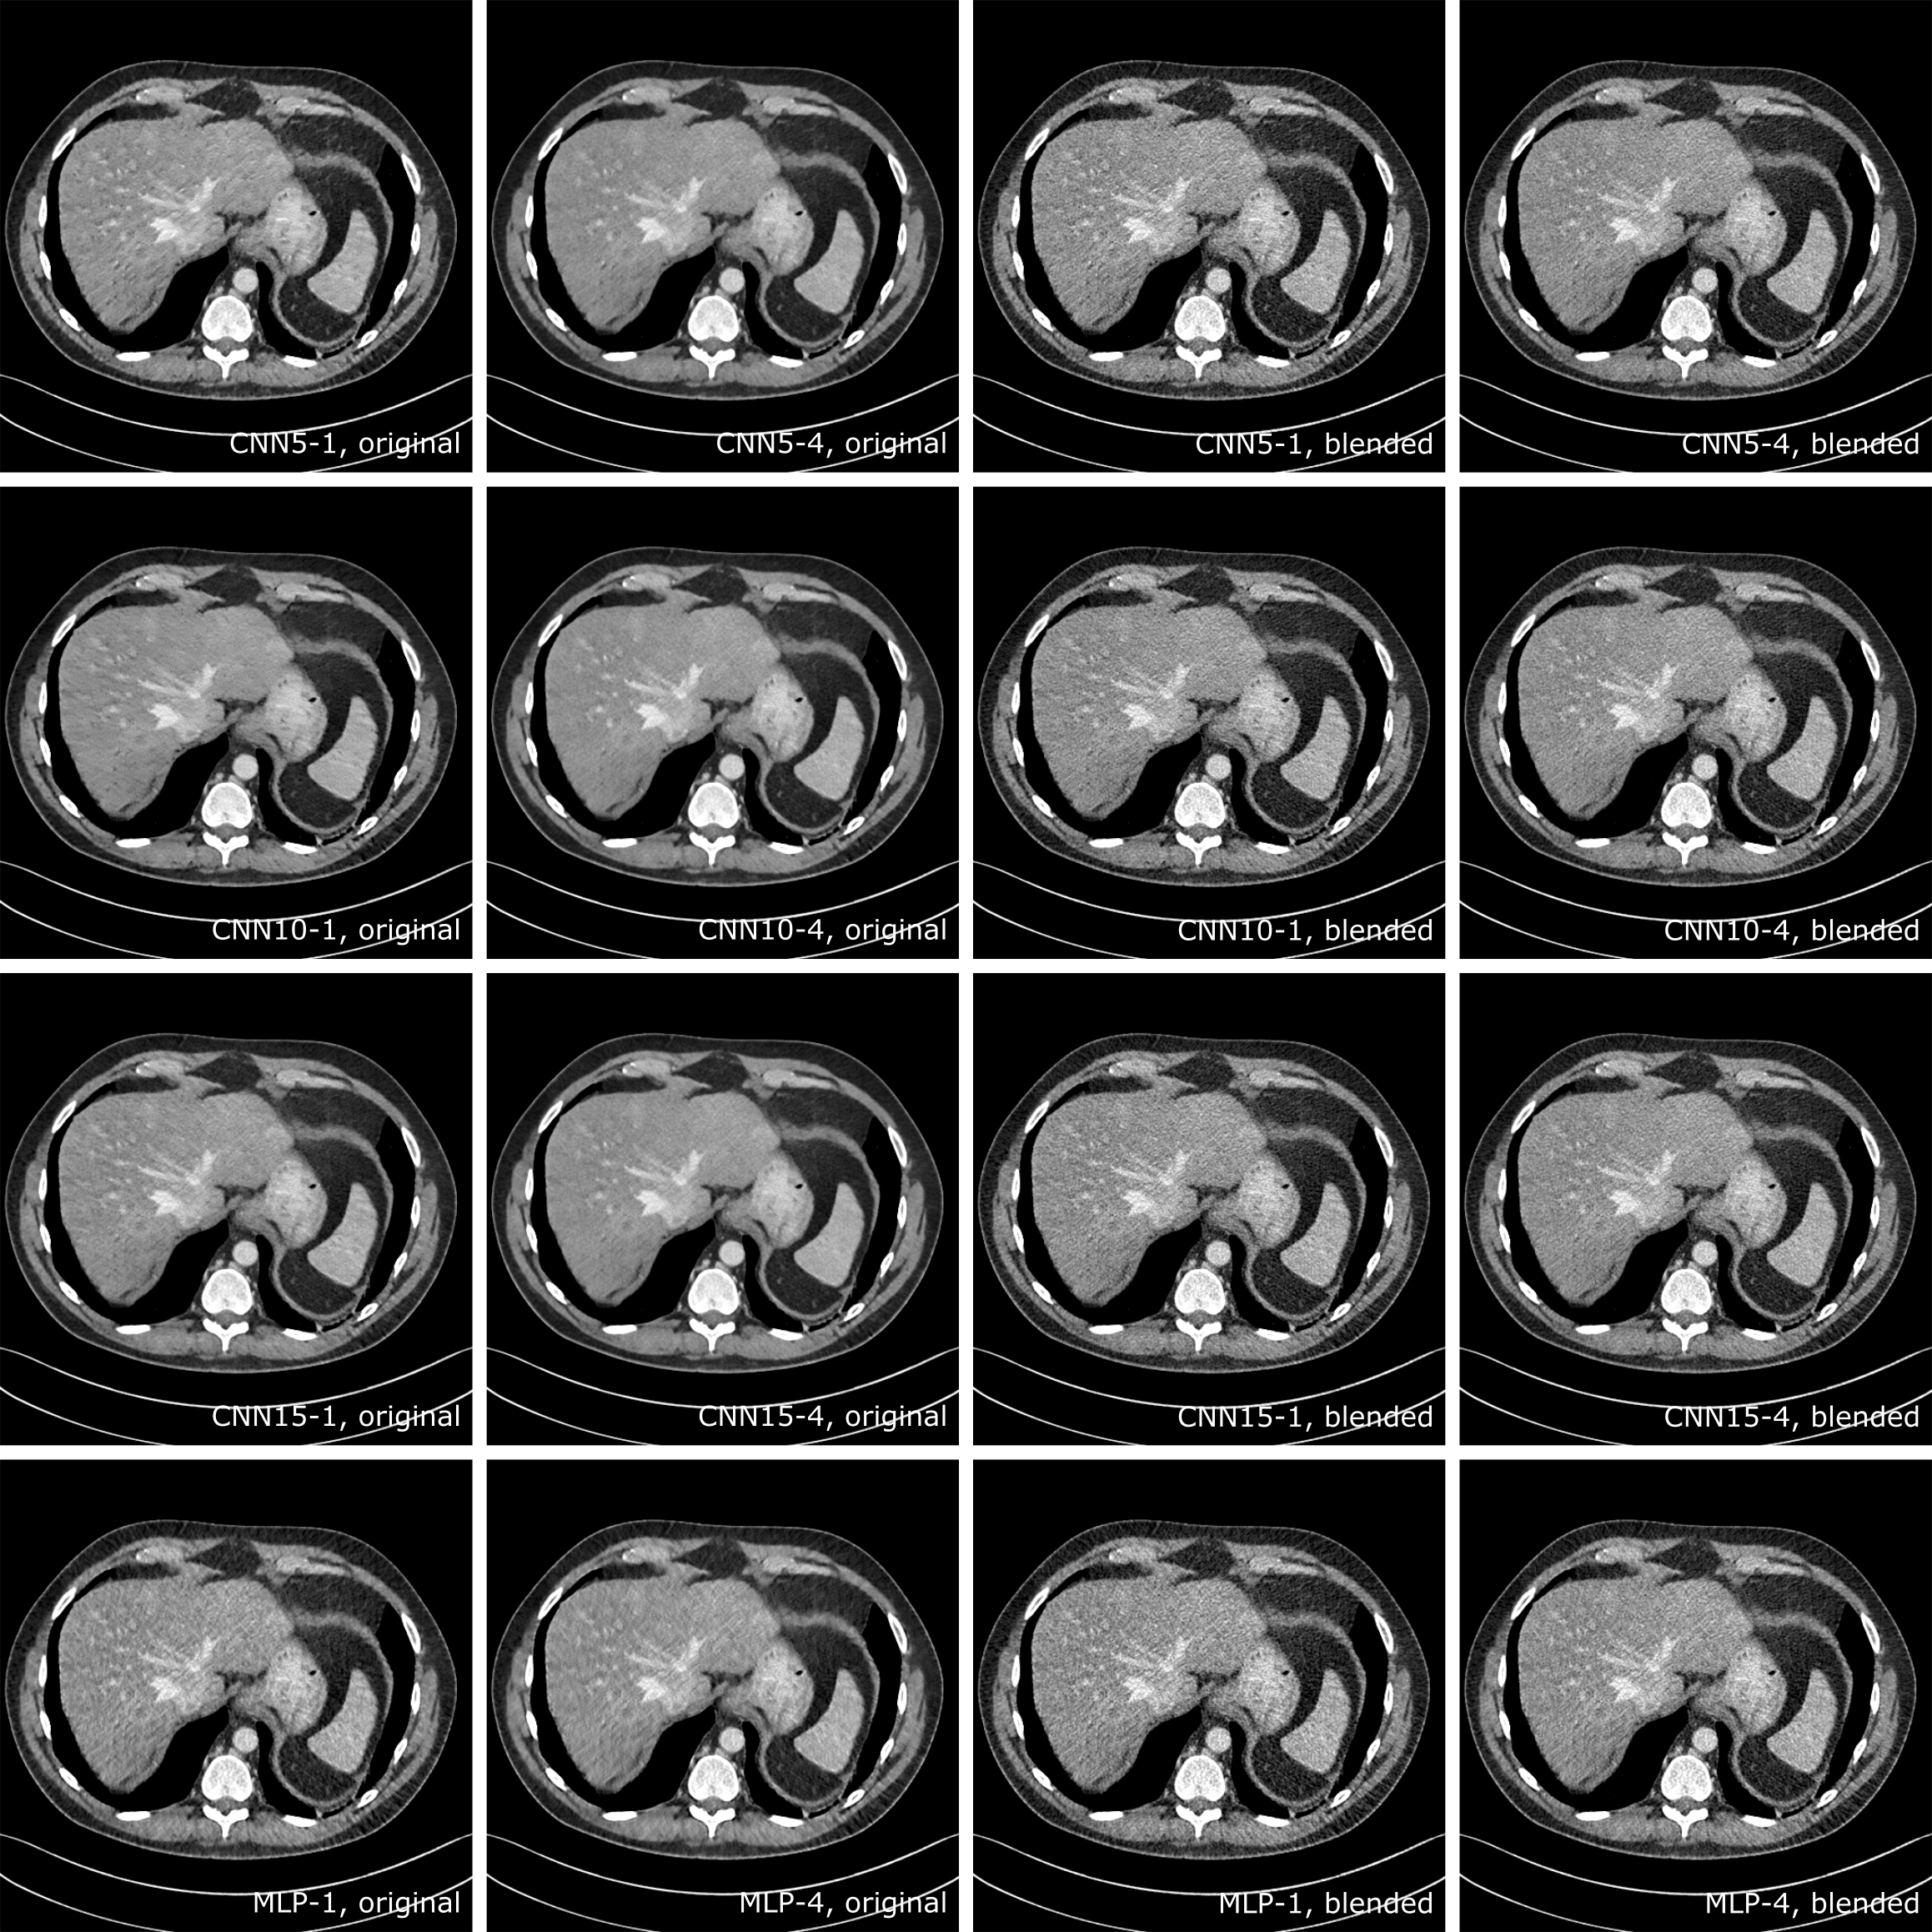

A slice that contained metastasis is selected to demonstrate the image quality improvement with cascaded CNNs visually. Figure 5 showed the corresponding normal-dose and original low-dose image of the selected slice, where the two metastasis contained in the slice were marked with white circles. The denoised results and corresponding 70% blended images are shown in Figure 6. Compared to the low-dose image, the visibility of the metastasis, especially the one near the chest, is greatly improved. There were noticeable blocky artifacts in CNN5-1 results in the liver, but it was greatly reduced by applying CNN cascades and almost gone in the results of CNN5-8. For the blended results, the improvement was not obvious as that on the original ones because of the increased noise level. Compared to CNN5-1, the cascaded CNNs gave more uniform liver areas with less speckles. No useful information lost such as blurring was observed with increased number of cascades.

Figure 7 demonstrated the result’s of cascaded CNN5, CNN10, CNN15 and MLP with the cascaded training scheme. There were strip artifacts on the liver for CNN10-1 and CNN15-1, which were removed in CNN10-4 and CNN15-4. The results from CNN5-4, CNN10-4 and CNN15-4 were visually similar, which indicated that the cascaded CNN could compensate for the lack of depth in a single CNN. The cascaded MLP results were also presented in Figure 7, which were more noisy than the CNN results. There was slightly reduced noise level in MLP-4 compared to MLP-1, which gave MLP-4 better PSNR and SSIM than MLP-1 as shown in Figure 4. The coronal and sagittal view for the denoised slices were provided in Figure 8, to demonstrate the uniformity across slices for the denoised results, despite of the fact that each slice were denoised independently.